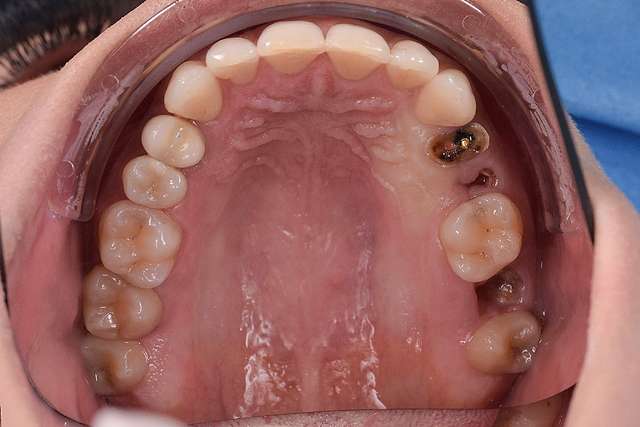

Implanturile dentare sunt tratamente indicate pentru dinti care nu mai sunt recuperabili. Implanturile au la baza lor principiul osteointegrarii, altfel spus, implantul se integreaza in os. Pentru o perioada lunga de timp, acesta a fost principalul obiectiv la nivel de industrie. Implantul sa fie integrat, sa fie plasat in functie de os. Astazi stim deja ca osteointegrarea este extrem de predictibilă si ne focusam pe alte elemente cheie care fac diferenta in calitate la un dinte restaurat cu implant dentar.

Chirurgia ghidata, ne faciliteaza o pozitie ideal pre-planificata, care nu tine cont doar de os, ci si de o pozitie optima in relatie cu viitorul dinte.Chirurgia ghidata înseamnă o precizie crescuta, care inseamna siguranta mai mare, timp operator mai scazut, si trauma mai mica. De asemenea focusul in acest tip de interventii a migrat spre reconstructia tesuturilor, care e pe termen lung are un impact mult mai mare atat estetic cat si biologic, inserarea implantului in sine fiind trivializata de folosirea ghidului chirurgical. Cazul de fata este un exemplu al acestui tip de abordare.